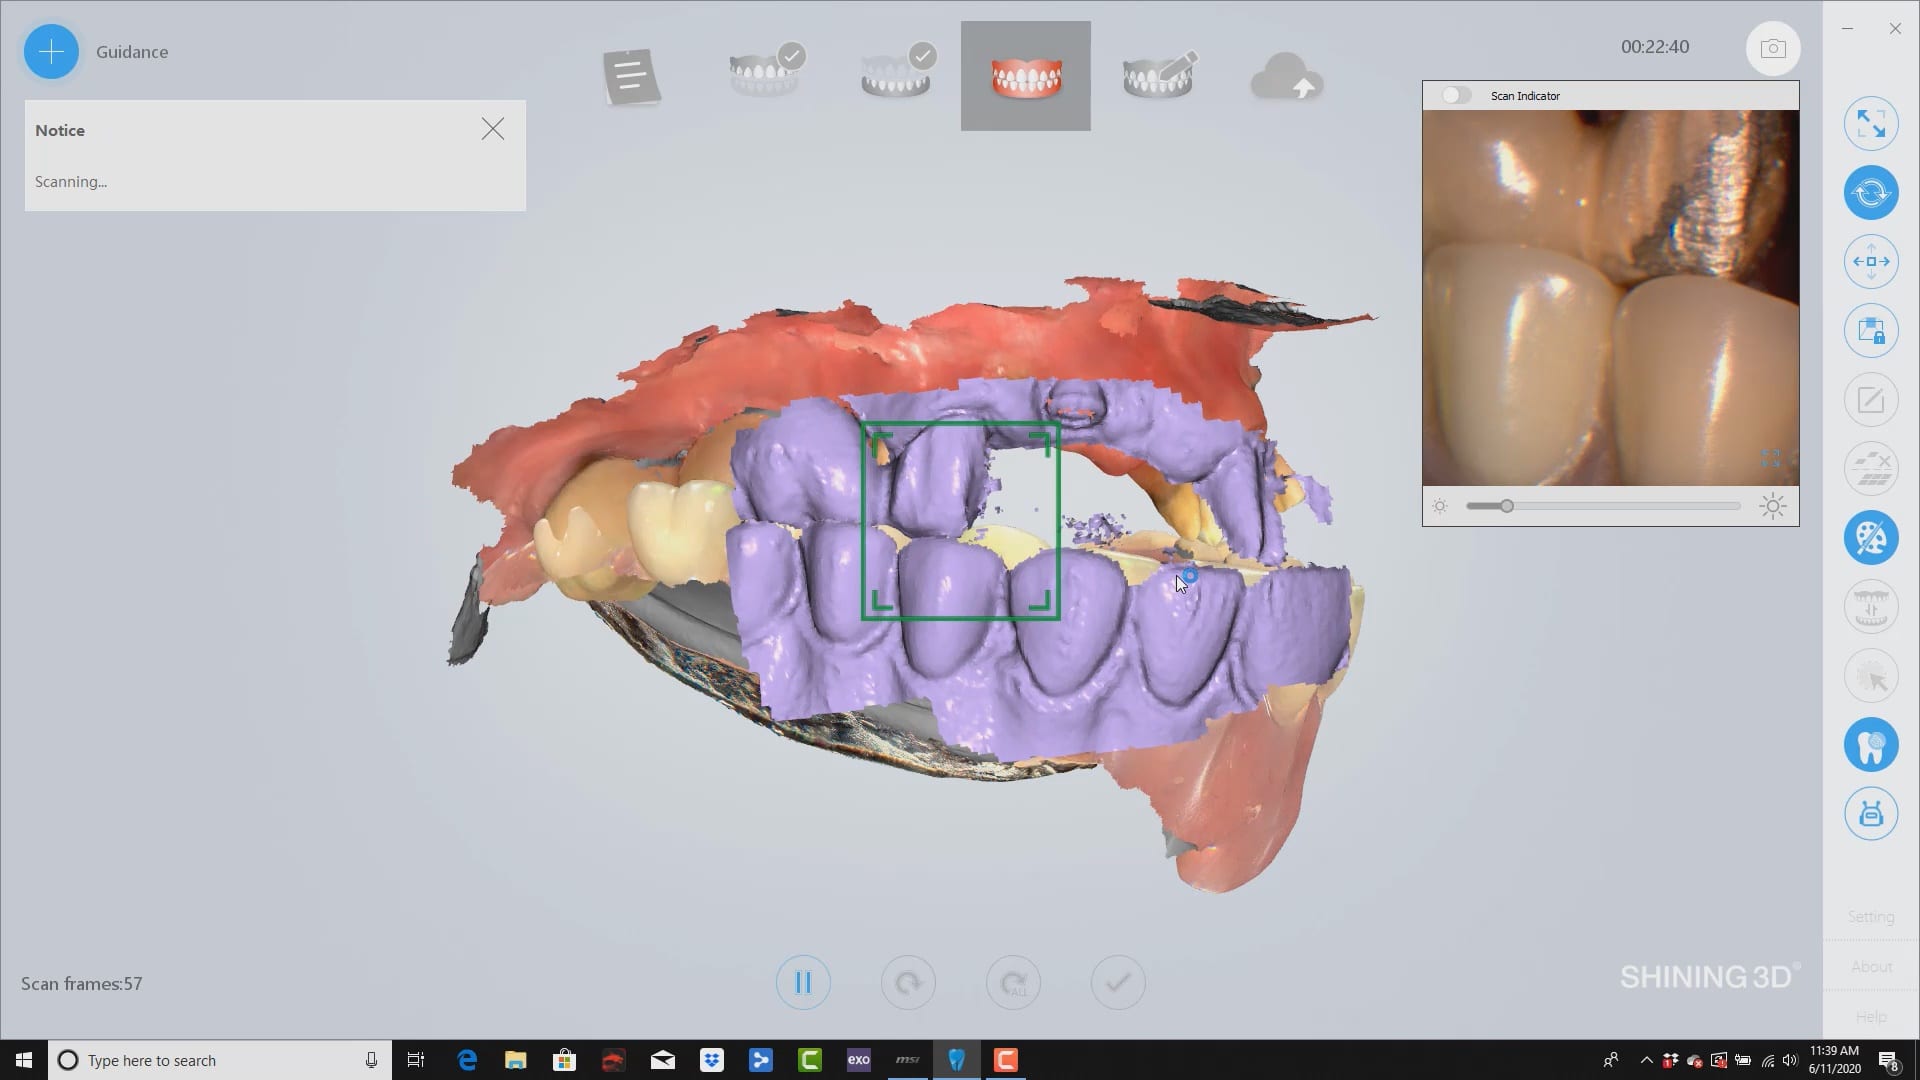

buccal bite taken intra-orally to mount arches at proper vertical dimension. you can see how the camera performs in this challenging case